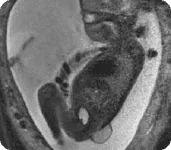

– Um diferencial técnico do curso, este módulo aborda a aplicação da análise 3D da marcha como ferramenta essencial para a avaliação biomecânica objetiva e o planejamento de intervenções individualizadas.

– Aprenda a interpretar os parâmetros cinemáticos e cinéticos que diferenciam os padrões de marcha idiopáticos dos padrões em mielomeningocele.

– Serão apresentados casos clínicos que ilustram a aplicação da análise tridimensional na escolha de órteses, indicação cirúrgica, evolução do tratamento e reavaliação pós-intervenção.